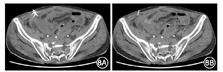

术后2个月余患者突发高热,体温42 ℃,骶尾部查体可及无波动感包块,经皮行穿刺术,未见脓液引出。CT引导下穿刺引流术,术中可见回结肠肠壁增厚,肠管周围积液,腹膜及肠系膜增厚伴盆腔渗出,未见脓液成分,穿刺后未留置引流管(图8)。血培养示脑膜败血伊丽莎白黄金杆菌阳性。经积极抗感染(亚胺培南联合甲硝唑静脉滴注)治疗后,患者体温始终波动于38~40 ℃。因患者病情再次加重,故进行第二次多学科讨论。